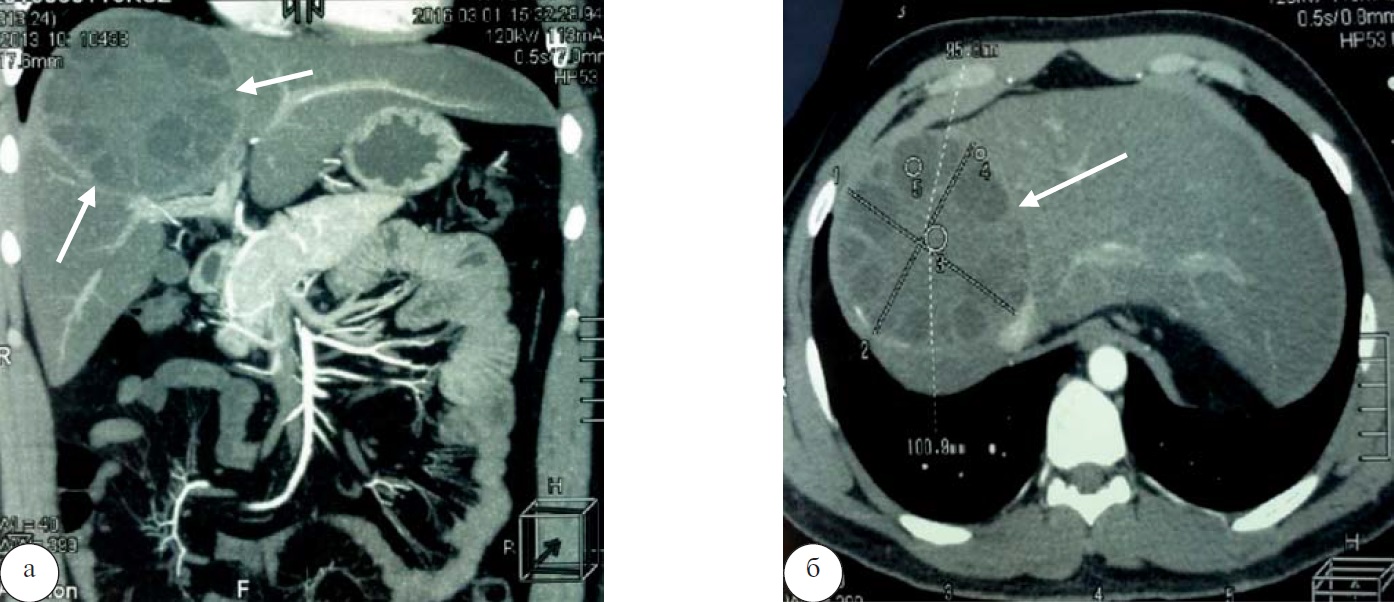

22.03.2016 под эндотрахеальным наркозом выполнена диагностическая лапароскопия для оценки степени поражения печени и определения возможности минимально инвазивного удаления кисты. При осмотре печени на передней поверхности в проекции S4, S7, S8 визуализируется кистозное образование, покрытое фибрином (рис. 4).

Рис. 4. Интраоперационный вид кисты на поверхности печени